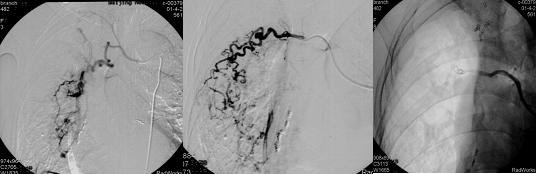

肺脏有两组血管,即肺循环和支气管循环。起于右心室动脉圆锥的肺动脉及其分支为低压系统,提供着肺脏约95%的血供。支气管动脉发自于主动脉,为高压系统,一般向肺脏提供约5%的血液,主要向气道和支撑结构供血。据统计,在大咯血病人当中90%的出血来自支气管循环,而出血来自肺循环者仅占10%左右。

根据最近的内外科系列综合研究,在上述常见病因中,引起大咯血的常见病因依次为:①支气管扩张(约占30%);②肺癌(约占20%);③肺结核(约占15%~20%)。

大咯血是由于支气管及其周围组织炎症和支气管阻塞所致的支气管壁的毁损和管腔扩张、变形,常伴有毛细血管扩张或支气管动脉和肺动脉络末支扩张等吻合,形成动脉瘤破裂,故可反复大量咯血。